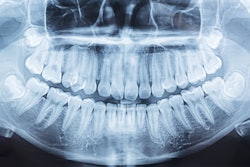

There may be a significant association between decayed, missing, and filled teeth (DMFT) index scores and a bone mineral density (BMD) diagnosis, according to a study published in BMC Oral Health.

Oral health was evaluated using the DMFT index and oral hygiene index-simplified (OHI-S) scores. Participants were grouped based on the number of surviving teeth, with low (< 20) and high (≥ 20) categories, they wrote.

The researchers found a statistically significant association between DMFT index scores and BMD diagnosis (F-statistic = 8.125, p < 0.001). The difference was most pronounced in the osteoporosis group compared to the other two groups. DMFT index scores were highest in the osteoporosis group (18.69) and lowest in the normal group (14.08, p < 0.001).

While the number of remaining teeth was lower in the osteoporosis and osteopenia groups than in the normal group (p < 0.001), the osteopenia group had a count closer to the normal group but significantly higher than the osteoporosis group. The group with the fewest remaining teeth also had lower total hip T-scores and significantly higher DMFT index scores (p < 0.001), they wrote.

"Tooth loss and dental decay rates were significantly high in patients with osteoporosis," they concluded.